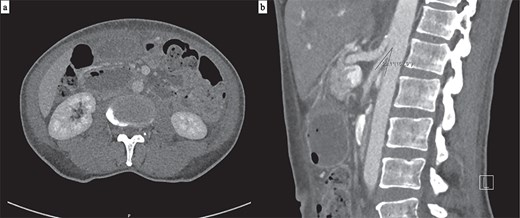

Progress CT showed interval improvement in gastric and small bowel dilatation, but persistent narrowing of the third duodenal segment beneath the SMA (Fig. 4). The patient tolerated reintroduction of oral feeding and was discharged after 2 days with no further nausea or vomiting. He remained well with no recurrence of obstructive symptoms four months later.

(a) Axial CT showing interval resolution of gastric dilatation with ongoing narrowing of the third duodenal segment between the aorta and SMA. (b) The aorto-mesenteric angle remains reduced at 22° on sagittal CT.